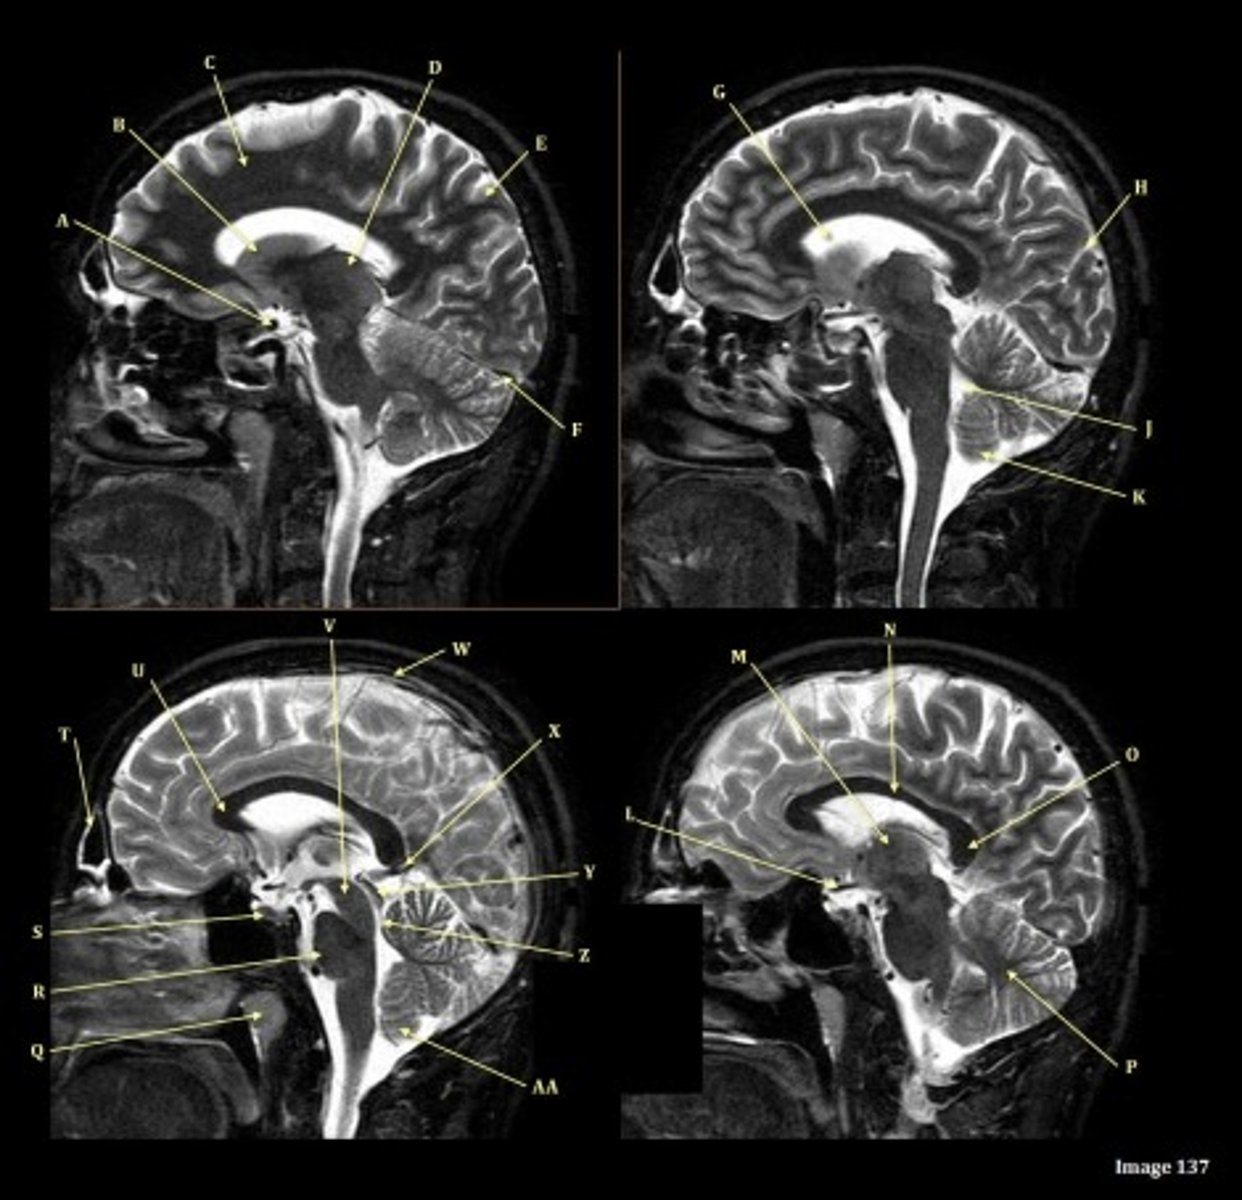

What type of sequence?

T2 FLAIR; Sagittal

A FLAIR (Fluid Attenuated Inversion Recovery) sequence is utilized to suppress signal from cerebrospinal fluid (CSF).

A

lateral ventricle

B

corpus callosum

C

thalamus

D- separates what

tentorium cerebelli- cerebrum (occipital and temporal lobes) from brainstem and cerebellum

E

fourth ventricle

F

medulla oblongata

V

Cerebral peduncle

W

superior sagittal sinus

X

vein of galen

Y

Inferior colliculus of midbrain,

just inferior to pineal gland / superior to the cerebral aqueduct

Letter N in Image 137 is pointing to what type of tissue?

White matter

The corpus callosum is the only white matter tissue structure found in the midline sagittal slice of the brain.